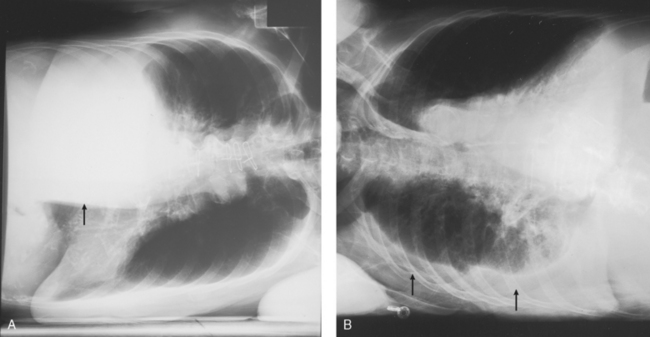

• Respiration: Inspiration. Neonates have an extremely fast respiratory rate and cannot hold their breath. Make the best attempt possible to perform the exposure on full inspiration (Fig. 28-31).

Fig. 28-31 Radiographs on inspiration and expiration in a neonate. A, Left side of chest is shown at full expiration. Note the lack of normal lung markings and the illusion of massive pulmonary disease. Diaphragm is not seen, and heart appears enlarged. B, Repeat radiograph of the same patient performed correctly at full inspiration. Diaphragm may be seen correctly at the level of the 10th posterior rib. The same technical factors were used for both exposures. (Courtesy Department of Radiology, Rochester General Hospital, Rochester, NY; from Cullinan AM, Cullinan JE: Producing quality radiographs, ed 2, Philadelphia, 1994, Lippincott.) Lippincott